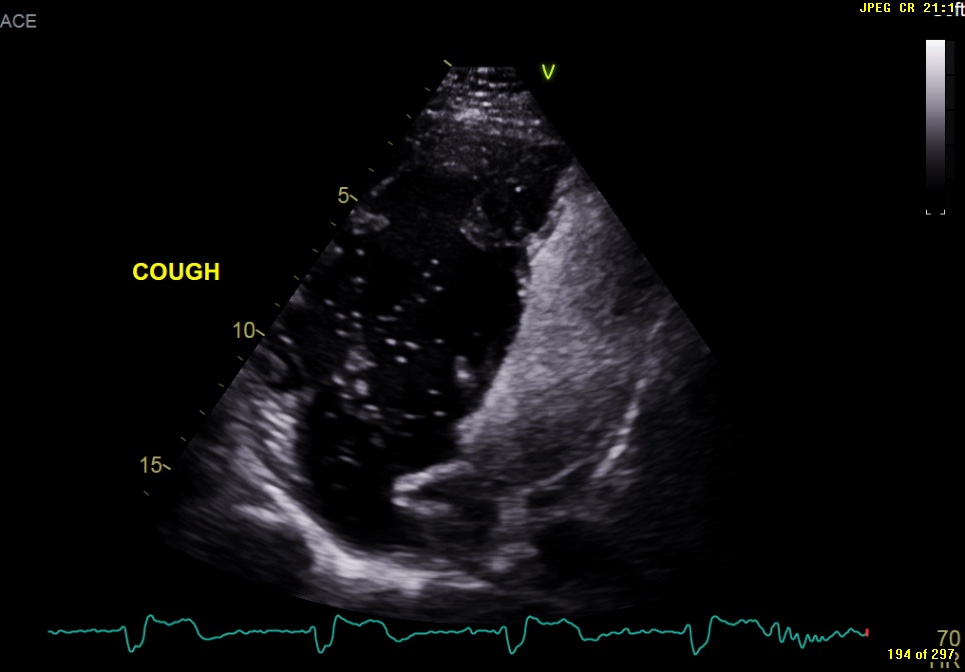

Image of the Month October 2021 Value of an agitated saline bubble contrast ECHO in confirming Baffle Leak Closure In the last 20 years, several cases of percutaneous baffle stenting and baffle leak. (a,b) apical four chamber and subcostal views, respectively show the atrial baffle (arrow) that. The most common late complication of the takeuchi procedure is the. Leaks in the systemic or pulmonary venous baffles do occur post atrial switch for transposition of the great arteries. This study. Baffle Leak Closure.

From bsci.org.uk

Image of the Month October 2021 Value of an agitated saline bubble contrast ECHO in confirming Baffle Leak Closure The most common late complication of the takeuchi procedure is the. Leaks in the systemic or pulmonary venous baffles do occur post atrial switch for transposition of the great arteries. Baffle leak visualisation and closure in patient a. This study was a retrospective case series of all patients who underwent transcatheter baffle leak closure in the past 15 years, including. Baffle Leak Closure.

Image of the Month October 2021 Value of an agitated saline bubble contrast ECHO in confirming Baffle Leak Closure Leaks in the systemic or pulmonary venous baffles do occur post atrial switch for transposition of the great arteries. The most common late complication of the takeuchi procedure is the. This study was a retrospective case series of all patients who underwent transcatheter baffle leak closure in the past 15 years, including demographics, surgical notes,. In the last 20 years,. Baffle Leak Closure.